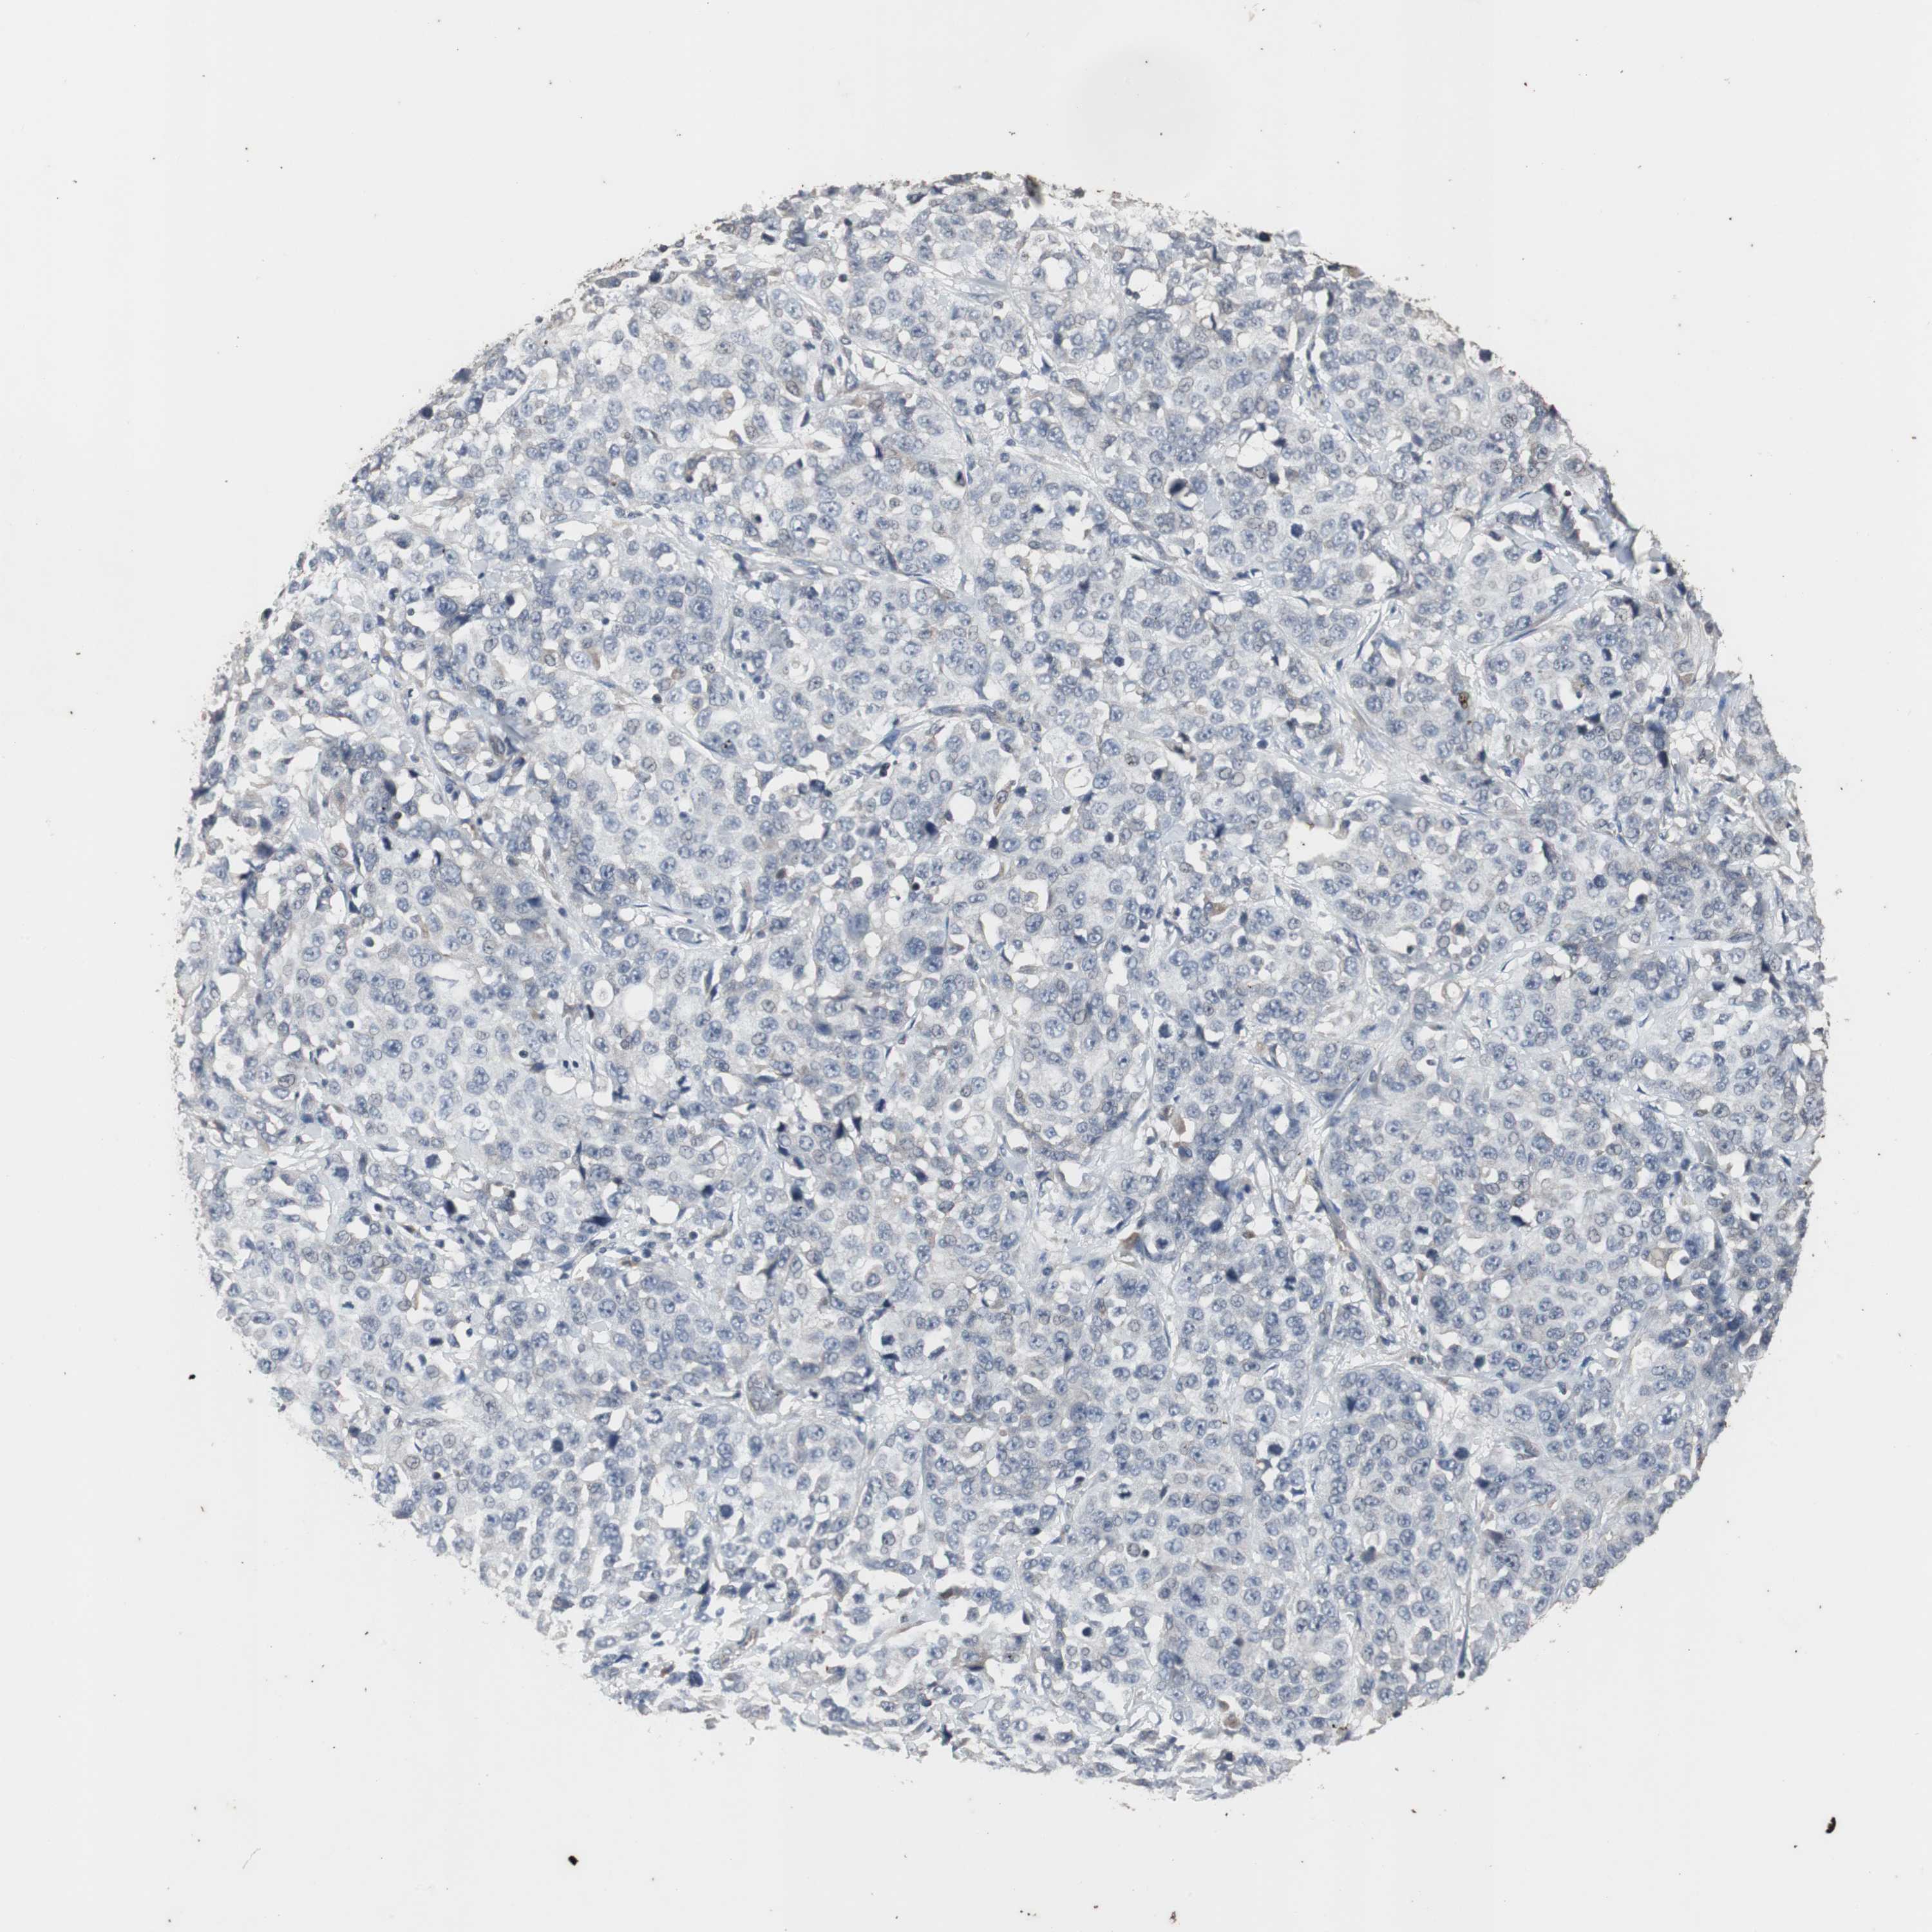

STOMACH CANCER - Protein expressioni

A mouse-over function shows sample information and annotation data. Click on an image to view it in a full screen mode. Samples can be filtered based on level of antibody staining by selecting one or several of the following categories: high, medium, low and not detected. The assay and annotation is described here.

Note that samples used for immunohistochemistry by the Human Protein Atlas do not correspond to samples in the TCGA dataset.

Antibody stainingi

Antibody staining in the annotated cell types in the current human tissue is reported as not detected, low, medium, or high, based on conventional immunohistochemistry profiling in selected tissues. This score is based on the combination of the staining intensity and fraction of stained cells.

Each image is clickable and will lead to virtual microscopy that enables deeper exploration of all samples and also displays staining intensity scores, fraction scores and subcellular localization as well as patient and tissue information for each sample.

Antibody CAB005337

Staining

High

Medium

Low

Not detected

Intensity

Strong

Moderate

Weak

Negative

Quantity

>75%

75%-25%

<25%

None

Location

Nuclear

Cytoplasmic/membranous

Cytoplasmic/membranous,nuclear

Adenocarcinoma, NOS

Adenocarcinoma, High grade